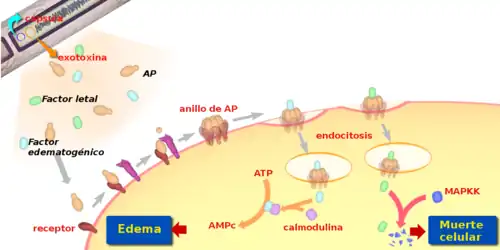

Hasta 1954 se pensaba que B. anthracis causaba la muerte por obstrucción capilar, debido a los elevados números de bacterias presentes en la sangre, pero se demostró que los síntomas podían darse incluso en la ausencia de infección, inyectando una exotoxina presente en el plasma de los organismos infectados en animales sanos.[6] Esta exotoxina, codificada por genes en el plásmido pXO1, consta de tres proteínas o factores diferentes, que actúan en concierto para interferir con la señalización celular en los macrófagos:[10][11]

- El antígeno protector (AP): Este factor se liga a los receptores celulares y forma un anillo heptámero en la superficie de la célula al que se adhieren los otros dos factores. A continuación se produce la endocitosis y los factores de virulencia pasan al interior de la célula.

- El factor edematógeno: Una vez en el interior de la célula este factor, activado por la calmodulina, incrementa la producción de la molécula mensajera AMPc a niveles anormales, causando una acumulación de fluidos en el interior y alrededor de la célula que da lugar al edema.

- El factor letal: Este factor recibe su nombre por causar la muerte en animales de experimentación. Actúa mediante la ablación de un fragmento de la citoquina MAPKK, que juega un papel crucial en el reclutamiento de otras células del sistema inmunológico para combatir la infección.